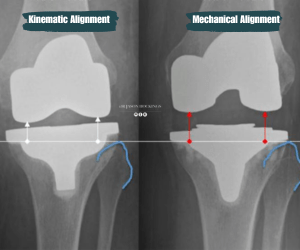

kinematic alignment vs mechanical alignment tka

In total knee replacement surgery, the goal is to replace the damaged parts of your knee with prosthetic components that restore stability, movement, and comfort. There are different ways to align these implants, and the two main techniques are mechanical alignment and kinematic alignment.

Mechanical alignment is the traditional technique used in knee replacement surgery. It positions the implants to form a straight line from the hip to the knee and down to the ankle, often called a neutral mechanical axis. Although this approach can create a symmetrical leg shape, it does not always reflect a person’s natural anatomy or the way their knee previously moved.

Kinematic alignment aims to restore the natural alignment and joint motion that were unique to your knee before arthritis developed. Instead of creating the same straight alignment for every patient, this technique works with your individual anatomy by respecting your original joint lines, ligament balance, and bone shape.

Using this approach, Dr Hockings incorporates detailed 3D imaging and surgical planning software to position the implants in a way that more closely reflects your pre-arthritic knee. This planning helps reduce the need for soft tissue releases and supports the natural pivot and glide of the joint.

The goal of kinematic alignment is to help the knee move in a way that feels closer to its natural pattern, which may support a smoother and more familiar walking style during recovery. While individual outcomes vary, kinematic alignment provides a more personalised approach compared with traditional mechanical alignment.